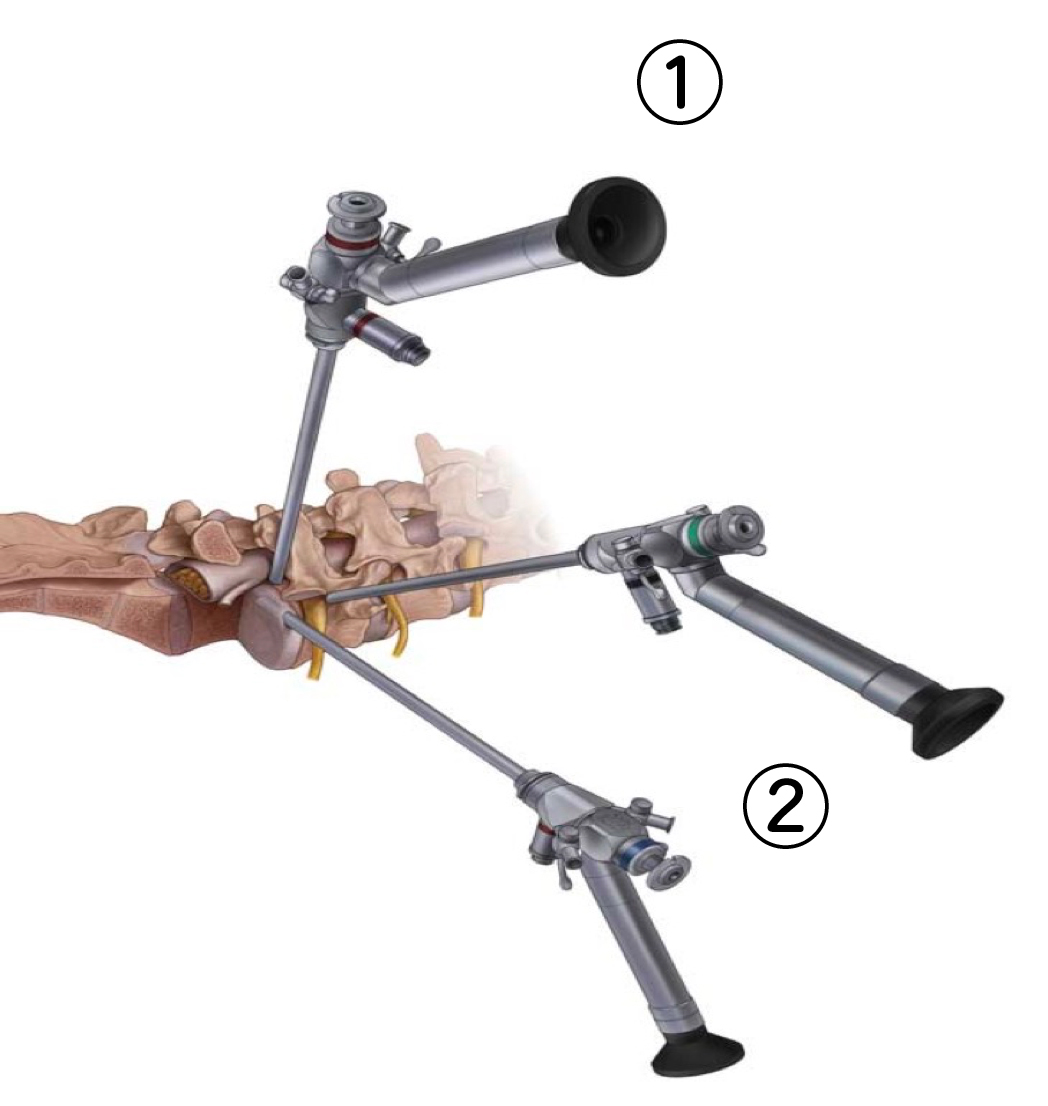

内視鏡システム | エム・シー・メディカル株式会社。脊椎内視鏡手術|平井整形外科クリニック|横浜市港北区綱島の。脊椎内視鏡センター|脊椎脊髄末梢神経外科|新百合ヶ丘総合病院。内視鏡手術の基礎から応用までを網羅した実用書。神経内視鏡手術 | 藤田医科大学 医学部 脳神経外科学講座。- タイトル: スタンダード 内視鏡手術- 出版社: MEDICAL VIEW1度も読んでいない新品ですが素人の自宅保管になりますので、完璧な新品を求めている方は落札をご遠慮下さい。裁断済み‼️スキャナーが必要です‼️皮膚科の処方ノート 2023。他にも多数出品しておりますので是非宜しくお願い致します。4冊セット 標準理学療法学。自己紹介文を必ず読んでから購入お願い致します。【裁断済み】 内科学 第12版 全6巻セット 朝倉書店。